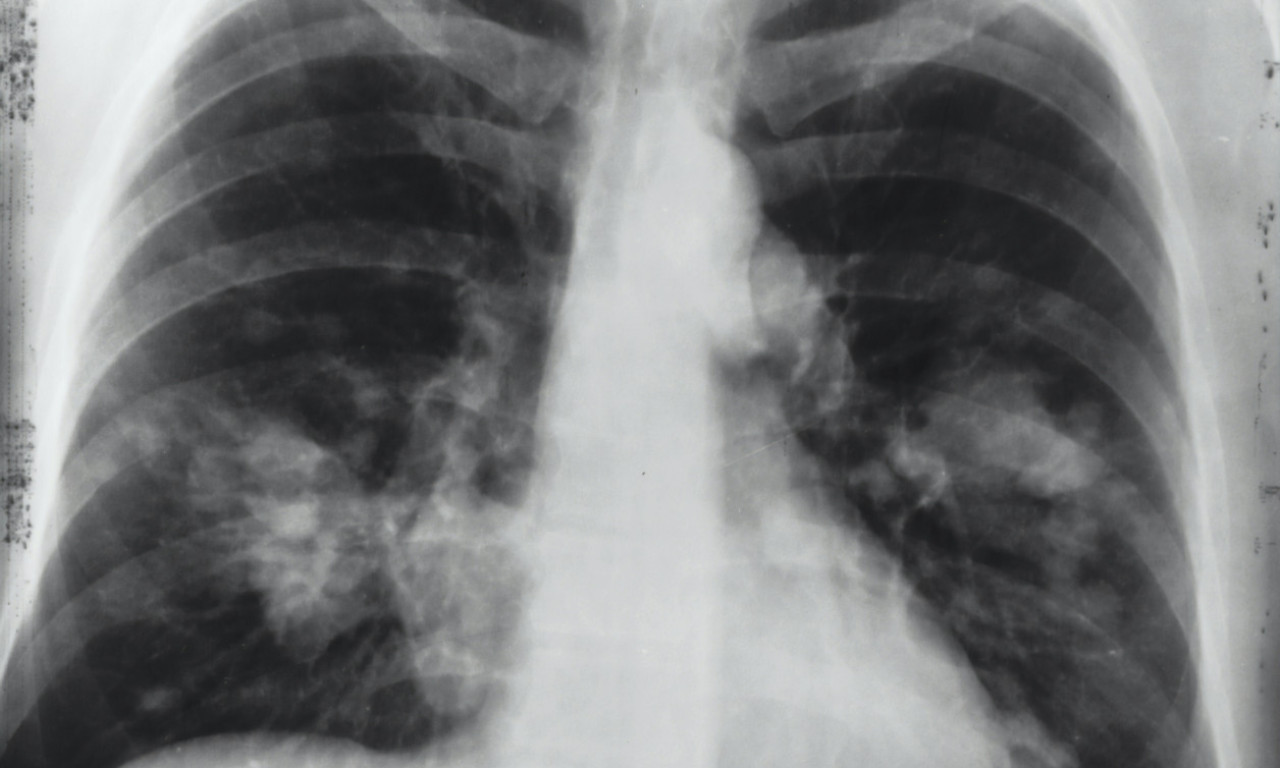

rak pluća

VEŠTAČKA INTELIGENCIJA OTKRIVA RAK PLUĆA MESEC DANA UNAPRED! Potrebno je uraditi osnovne medicinske analize

Na svaka dva sata u Srbiji jedna osoba premine od KARCINOMA PLUĆA! Od jeseni počinje "borba" u SRBIJI, a evo i kako

Svetski dan borbe protiv raka pluća obeležava se svake godine 1. avgusta.

Rak pluća je vodeći uzrok smrti od raka u svetu, a godišnje ima 1,8 miliona smrtnih slučajeva od kancera pluća

ALARMANTNI PODACI U SRBIJI! Od RAKA PLUĆA oboli 7.000 SRBA godišnje, što nas stavlja na drugo mesto u Evropi

CRNA STATISTIKA: 70% obolelih RAK PLUĆA otkrije tek kad su ŠANSE ZA IZLEČENJE MINIMALNE, ovo je NAJVEĆI PROBLEM

Srbija drži PRVO MESTO u Evropi po smrtnosti od KARCINOMA PLUĆA - zašto je to tako?

Ukoliko se otkrije na vreme, ova opaka bolest je izlečiva